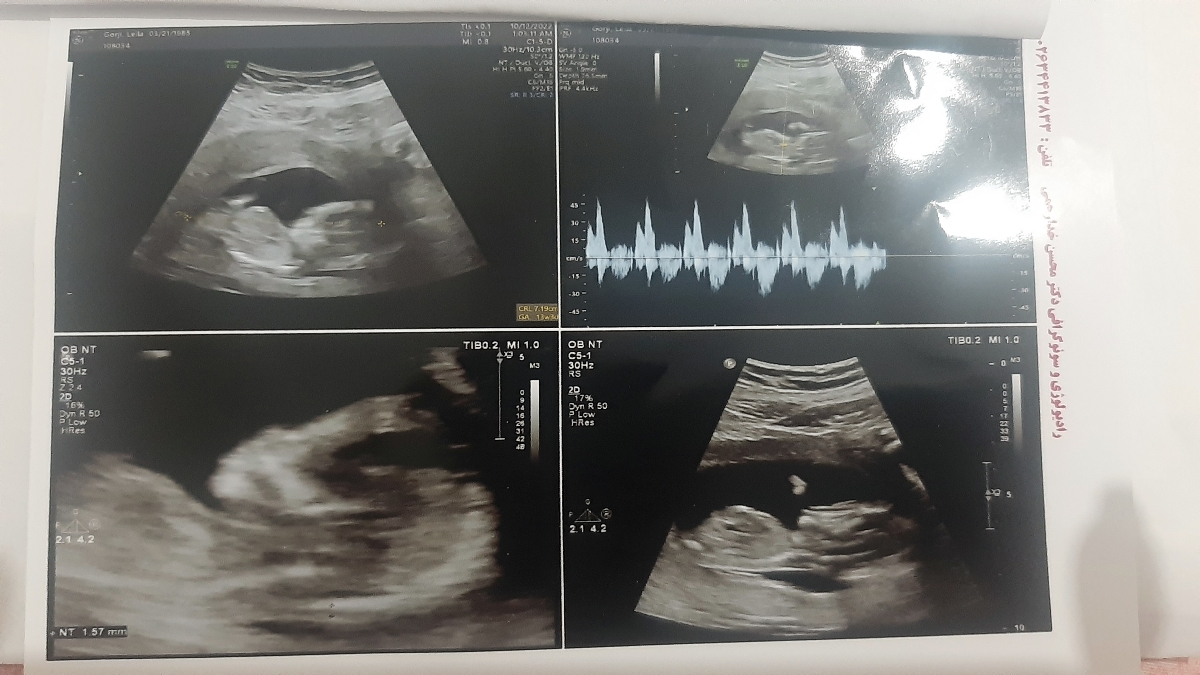

تشخیص جنسیت از روی سونو ان تی

عکس سونو رو میزارم ممنون میشم نظرتون رو در مورد جنسیت بگین